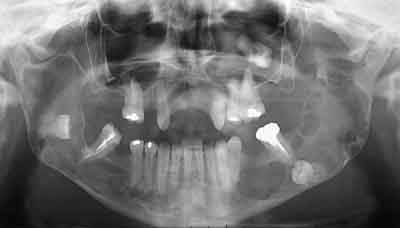

Diagnotic extemporané : kératokystes (!). Les dents incluses se sont donc avérées être un piège diagnostic! Le traitement s'est de ce fait contenté d'un curetage appuyé des paroies osseuses, conservation des 2 nerfs dentaires et, en raison de la taille des kystes mandibulaires et du risque de fracture post-opératoire, nous avons y avons associé une greffe (hydroxyapatite + os autologue (crête illiaque) + PRP) au niveau mandibulaire uniquement (photos 2 et 3)et blocage intremaxillaire pendant 15 jours.

Les suites ont été simples, la reminéralisation des kystes est actuellement en cours (photo 4) et la sensibilité des V3 est normale.

on dirai que t'as comblé ta branche montante sur la pano, est-ce bien necessaire?;)